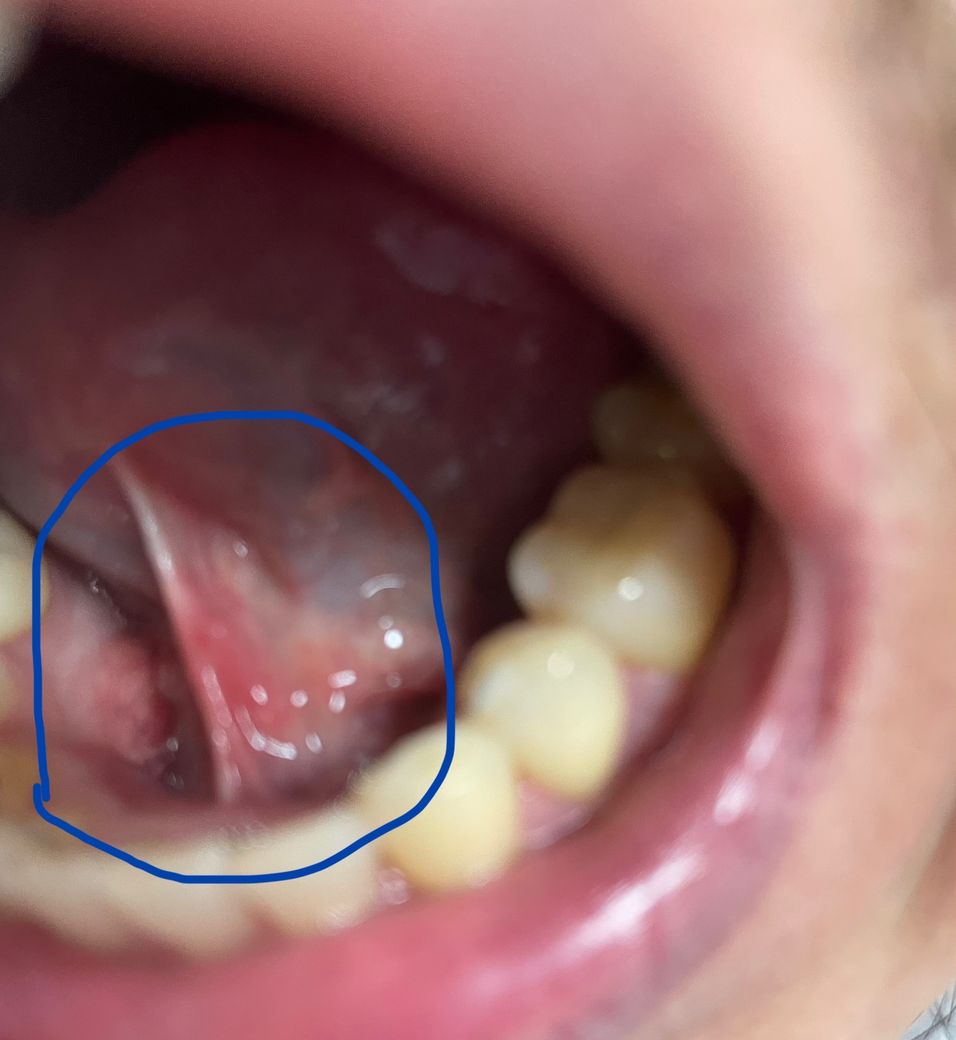

후두경하고나서 후두쪽라인에 림프절이 있다고해서 저약을 받아 복용중이구요. 복용3일차입니다. 다름이아니오라 사진과같이 설소대쪽에 이틀전부터 저렇게 빨갛고 밥먹을때도 약간 통증이 있습니다. 저약먹으면 저기에도 효능이 있나요?

• 사진상 설소대 하방 점막이 국소적으로 충혈되고 약간 부어 있는 소견입니다. 궤양이나 고름이 명확히 보이지는 않아 보이며, 전형적인 세균성 농양보다는 기계적 자극이나 경미한 점막염 가능성이 더 높아 보입니다. 후두경 검사 후 발생했다면 기구 접촉에 의한 마찰, 건조, 일시적 염증 반응이 흔한 원인입니다.

처방 약은 비스테로이드성 소염진통제, 세팔로스포린계 항생제, 위장약으로 보입니다. 항생제는 세균성 감염이 동반된 경우에 효과가 있으나, 단순 자극성 염증이나 외상성 점막염에는 뚜렷한 치료 효과가 제한적입니다. 현재 소견만으로는 항생제가 설소대 병변을 직접적으로 치료한다고 단정하기는 어렵습니다.

대부분은 3일에서 7일 이내 자연 호전됩니다. 자극적인 음식, 음주, 흡연은 피하고 미지근한 물 가글 정도로 관리하십시오. 통증이 심해지거나, 궤양이 깊어지거나, 고름·발열·경부 종창이 동반되면 구강외과 또는 이비인후과 재진이 필요합니다. 1주 이상 지속되면 감염, 타석증, 드물게 종양성 병변 감별이 필요합니다.